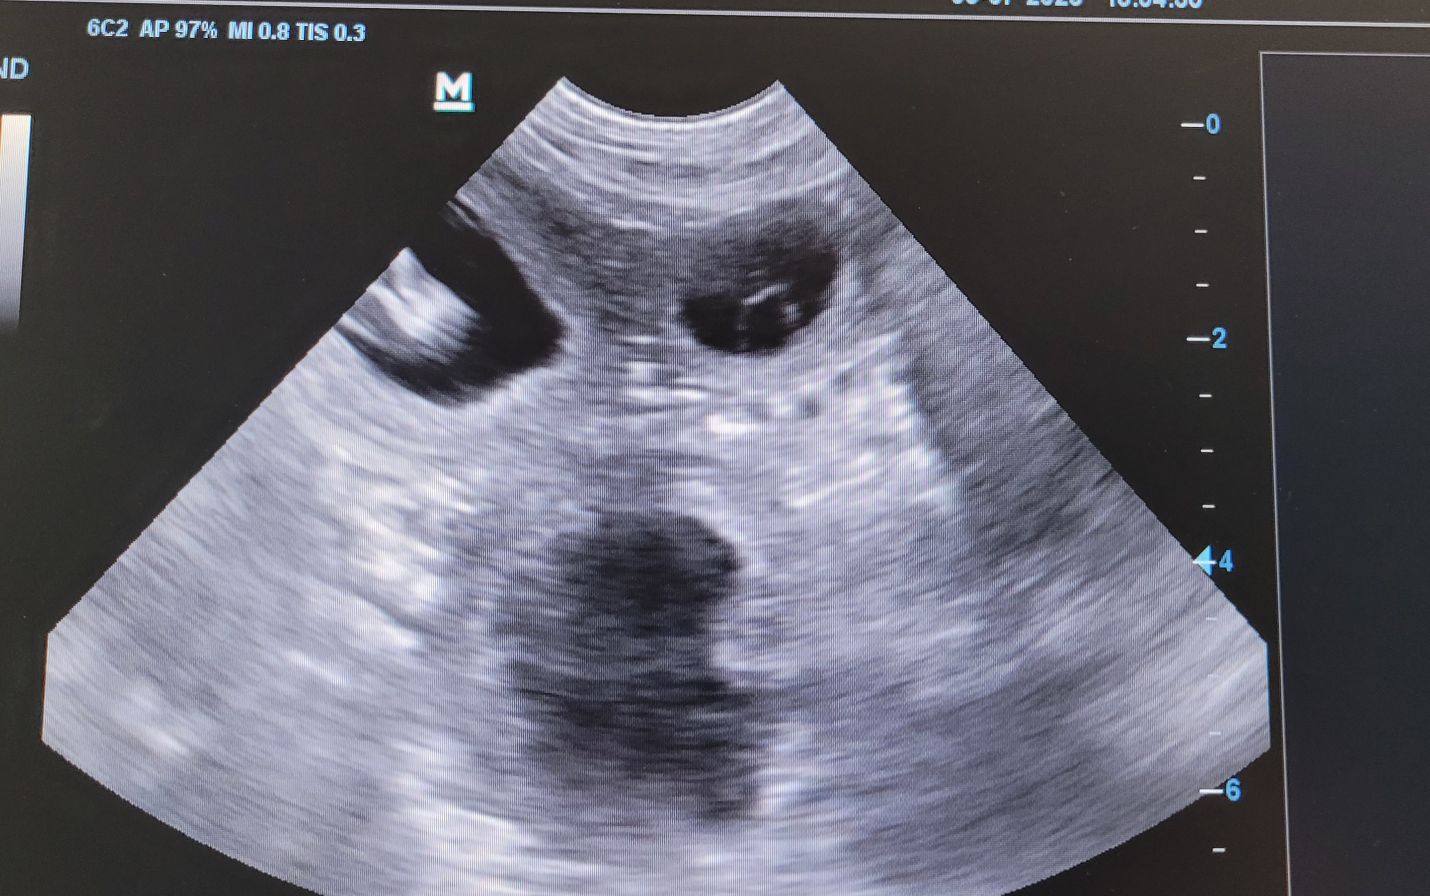

Am 30.Tag der Trächtigkeit sind die Früchte circa 1,6-2,1 cm groß und Augenlider,Ohrmuscheln und Lippen entwickeln sich !Am 03.07. wissen wir mehr ,--dann fahren wir zum Ultraschall !!!

Juhuhuhuh!!!Violet ist tragend von Dancer !!! Wir freuen uns riesig!!!!